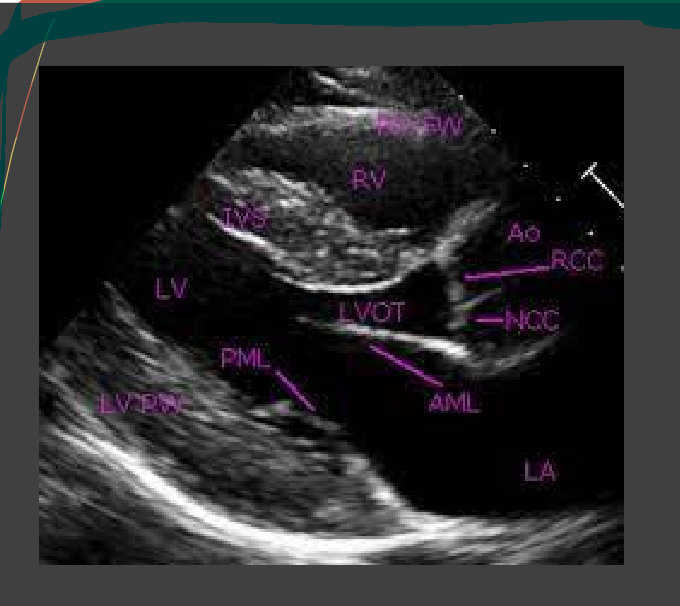

what are the white labels

RV

LA

LV

LVOT

AO

What is this view

parasternal long axis of the heart